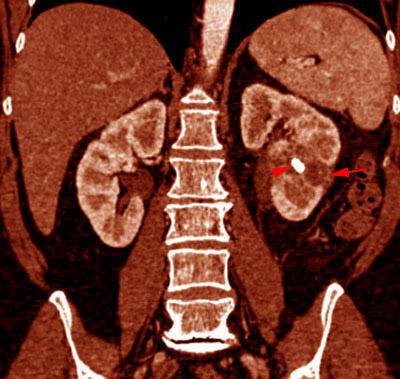

Pielonefritis xantogranulomatosa

VR seccional. Visión coronal anterior. TC contrastado en fase venosa mostrando litiásis renal izquierda (punta de flecha) junto a cambios necroticos (flecha). Signos inflamatorios afectando a fascia de Gerota y espacio perirrenal